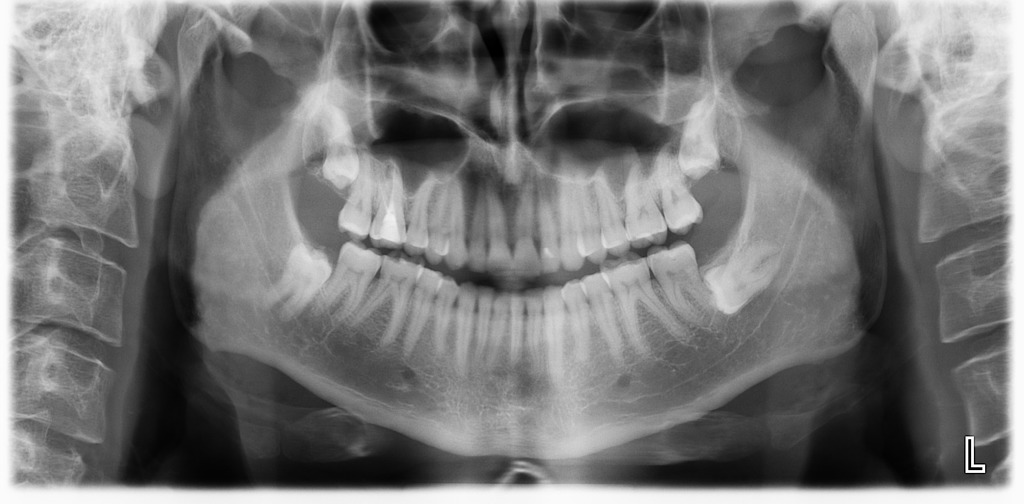

The most common X-Ray required is an OPG, which will show all the wisdom teeth, it will reveal signs of infection or other pathology, it will highlight the relation of the wisdom tooth to the adjacent molars and will show the proximity of the roots of the wisdom tooth to the inferior dental nerve.